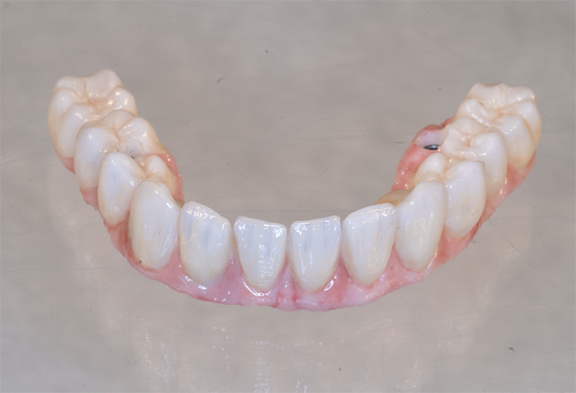

An implant-retained and implant-supported removable prosthesis may be fabricated by using a bar or a conical, titanium abutment with a 5-degree taper (Figure 18).49 In the next case, a fixture-level impression was made and records were registered and sent to the laboratory with the abutments (preselected based on the height of the mucosal cuff) for framework and prosthesis fabrication.49 The prosthesis had recesses on its intaglio surface to permit pickup of the abutment caps (Figure 19).49 The abutments were attached to the implants in the mouth (Figure 20). A jig/index provided by the laboratory (Figure 21) was used to seat the abutments intraorally so that they were positioned exactly as they were on the master cast. Gold caps were placed over the abutments and were picked up in the prosthesis intraorally (Figure 22).49 (Gold caps that fit over the abutments provide excellent retention, which improves over time.)50 The prosthesis was adjusted, finished, polished, and placed in the mouth (Figure 23). The prosthesis was entirely supported by the implant abutments.49 It had excellent retention and stability (almost like a fixed restoration) because it was entirely implant-supported; yet, it was removable.49

Fig 18. Conical abutments were used to retain an implant-supported removable prosthesis.

Figure 18

Fig 19. Recesses permitted pickup of the abutment caps.

Figure 19

Fig 20.  Abutments were attached to implants in the mouth (Atlantis Conus abutments, Dentsply Sirona).

Figure 20

Fig 21. A jig was provided to optimally position the abutments intraorally.

Figure 21

Fig 22. The abutment caps were picked up in the prosthesis.

Figure 22

Fig 23. The prosthesis was placed in the patient’s mouth.